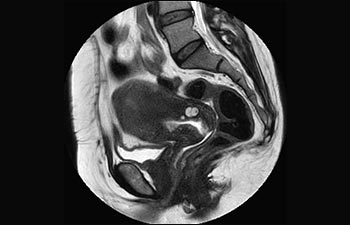

Frau Silvia Schiffer, leitende Radiologin bei Radiologie Schiffer in Deutschland, berichtet über ihre Erfahrungen mit dem Ingenia Prodiva 1.5T MR-System.

Sehen Sie selbst, was die ersten Nutzer von Ingenia Prodiva 1.5T über ihre Erfahrungen mit dem System und dessen Auswirkung auf ihre radiologische Praxis berichten.